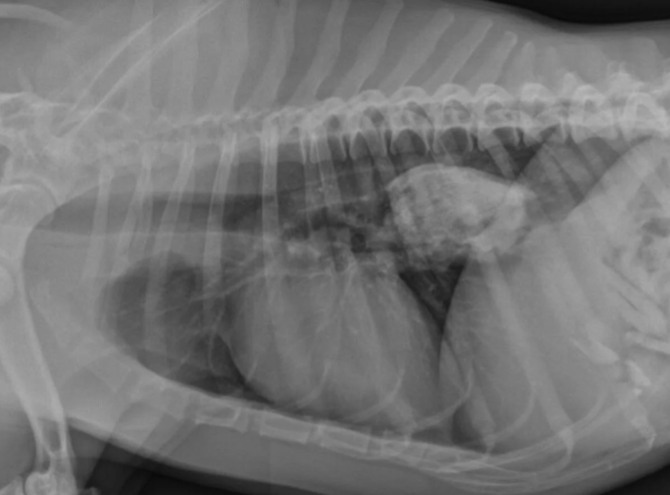

Важно: Мегаэзофагус вызывает именно срыгивание. Если вы видите, что питомец срыгивает непереваренной пищей — это повод для срочной диагностики